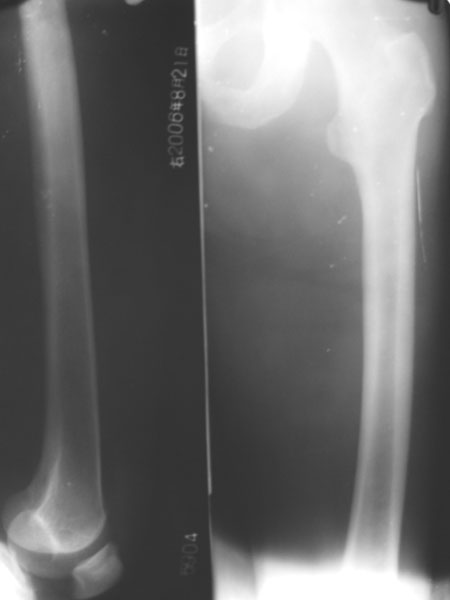

患者,男,48岁,右大腿及右膝关节功能障碍就诊,病人入院时,由家属背入,消瘦,右膝及右髋关节活动障碍,不能伸直,以下是右股骨和双髋关节平片.

看不清呀。软组织肿胀明显,见点样死骨。

右侧股骨头及髋臼相邻关节面骨质见明显破坏,边界不清,关节面皮质缘大部消失,无明显骨质增生,间隙变窄,周围软组织明显肿胀.(图像不理想)

考虑:右髋关节结核可能性大.

看不太清楚,以前是否有外伤史,髋臼缘似可见骨质增生,不能完全排除退行性变。

从本片看右髋关节周缘骨质增生,本片似乎没有骨质破坏及骨疏,关节间隙变窄,病人年龄较小,与症状结合病人病程应很长,关节僵硬可能是由长期不活动发生关节纤维性强直,而且软组织内有异物,考虑应为创伤性骨关节炎,结核待排,慢性化脓性关节炎亦考虑

该病人无外伤史,至于异物,没有的,那是短裤上的拉链,短裤没有完全退下来,该患者家中有结核病人,现该患者病程为一个多月左右,该患者照是强迫体位,右膝关节不能伸直,所以只有照了一个蛙式位,但不是很标准.

首先考虑髋关节结核.因为髋骨呈虫噬样破坏,并且右大腿软组织内见斑点状钙化.

我认为结核不怎么象..现在的这个病人病程短以骨质硬化和软组织肿胀为主.而结核一般以骨质疏松为主.我个人认为骨髓炎也是很应该考虑的.